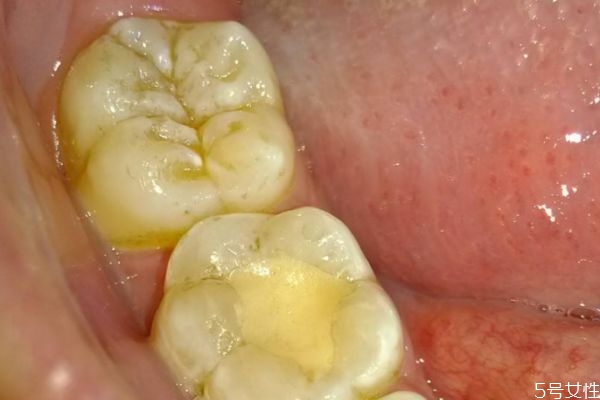

牙齦腫痛的絕大部分原因,還是牙結(jié)石或者說是軟垢的刺激。牙齒表面不干凈,軟垢以及結(jié)石的堆積,就會刺激這個牙齦,刺激牙齦的血管擴(kuò)張,然后牙齦就會紅腫出現(xiàn)疼痛,經(jīng)常發(fā)生牙齦腫痛,必須要到醫(yī)院來進(jìn)行檢查。針對具體的情況,進(jìn)行具體的處理。如果是軟垢或者結(jié)石的刺激影響,那么主要的治療方法,還是進(jìn)行洗牙潔牙,或者說是超聲波潔治,如果長期出現(xiàn)牙齦腫痛,不處理的話病人一般會自己,第一次自己很難受,然后第二呢牙齦出血,也會對你的社交造成一些困擾。第三長期的牙齦腫痛,牙齒的炎癥得不到有效的控制,會使牙槽骨以及牙齦萎縮,那么牙齒會松動,牙齒松動以后,一般來說絕大部分情況,沒有辦法再恢復(fù)正常,會造成牙齒脫落。

牙齦腫的危害性是特別嚴(yán)重的,對于患者的牙齦健康損害嚴(yán)重,病發(fā)期間給患者帶來了困擾,甚至?xí)蓴_到工作以及生活,提醒各位朋友需要將牙齦腫了解透徹,平時的生活中多了解相關(guān)的誘發(fā)起因,生活中誘發(fā)牙齦腫的起因特別的復(fù)雜,主要包括牙周膿腫、牙齦膿腫、智齒冠周炎、根尖周炎等,這是都是常見的病因,很多人會因為這些病癥而出現(xiàn)牙齦腫痛的癥狀,從而侵害了牙齒及牙齦部位的健康。如果患者自身存在牙齦或者是牙周組織方面的慢性炎癥,特別是患者的機體抵抗力嚴(yán)重下降、天氣干燥、進(jìn)食辛辣及刺激性嚴(yán)重的食物時,都會導(dǎo)致原有的慢性炎癥產(chǎn)生急性的發(fā)作,繼而誘發(fā)了牙齦腫痛的癥狀,傷害了患者的牙齦健康,為此朋友們要注意口腔的衛(wèi)生,正確的刷牙,還要注意提早做一些牙齦腫痛的預(yù)防工作,這樣才能減輕牙齦腫的病發(fā)率,從而保護(hù)了人們的牙齦健康,遠(yuǎn)離了疾病的困擾和損害。